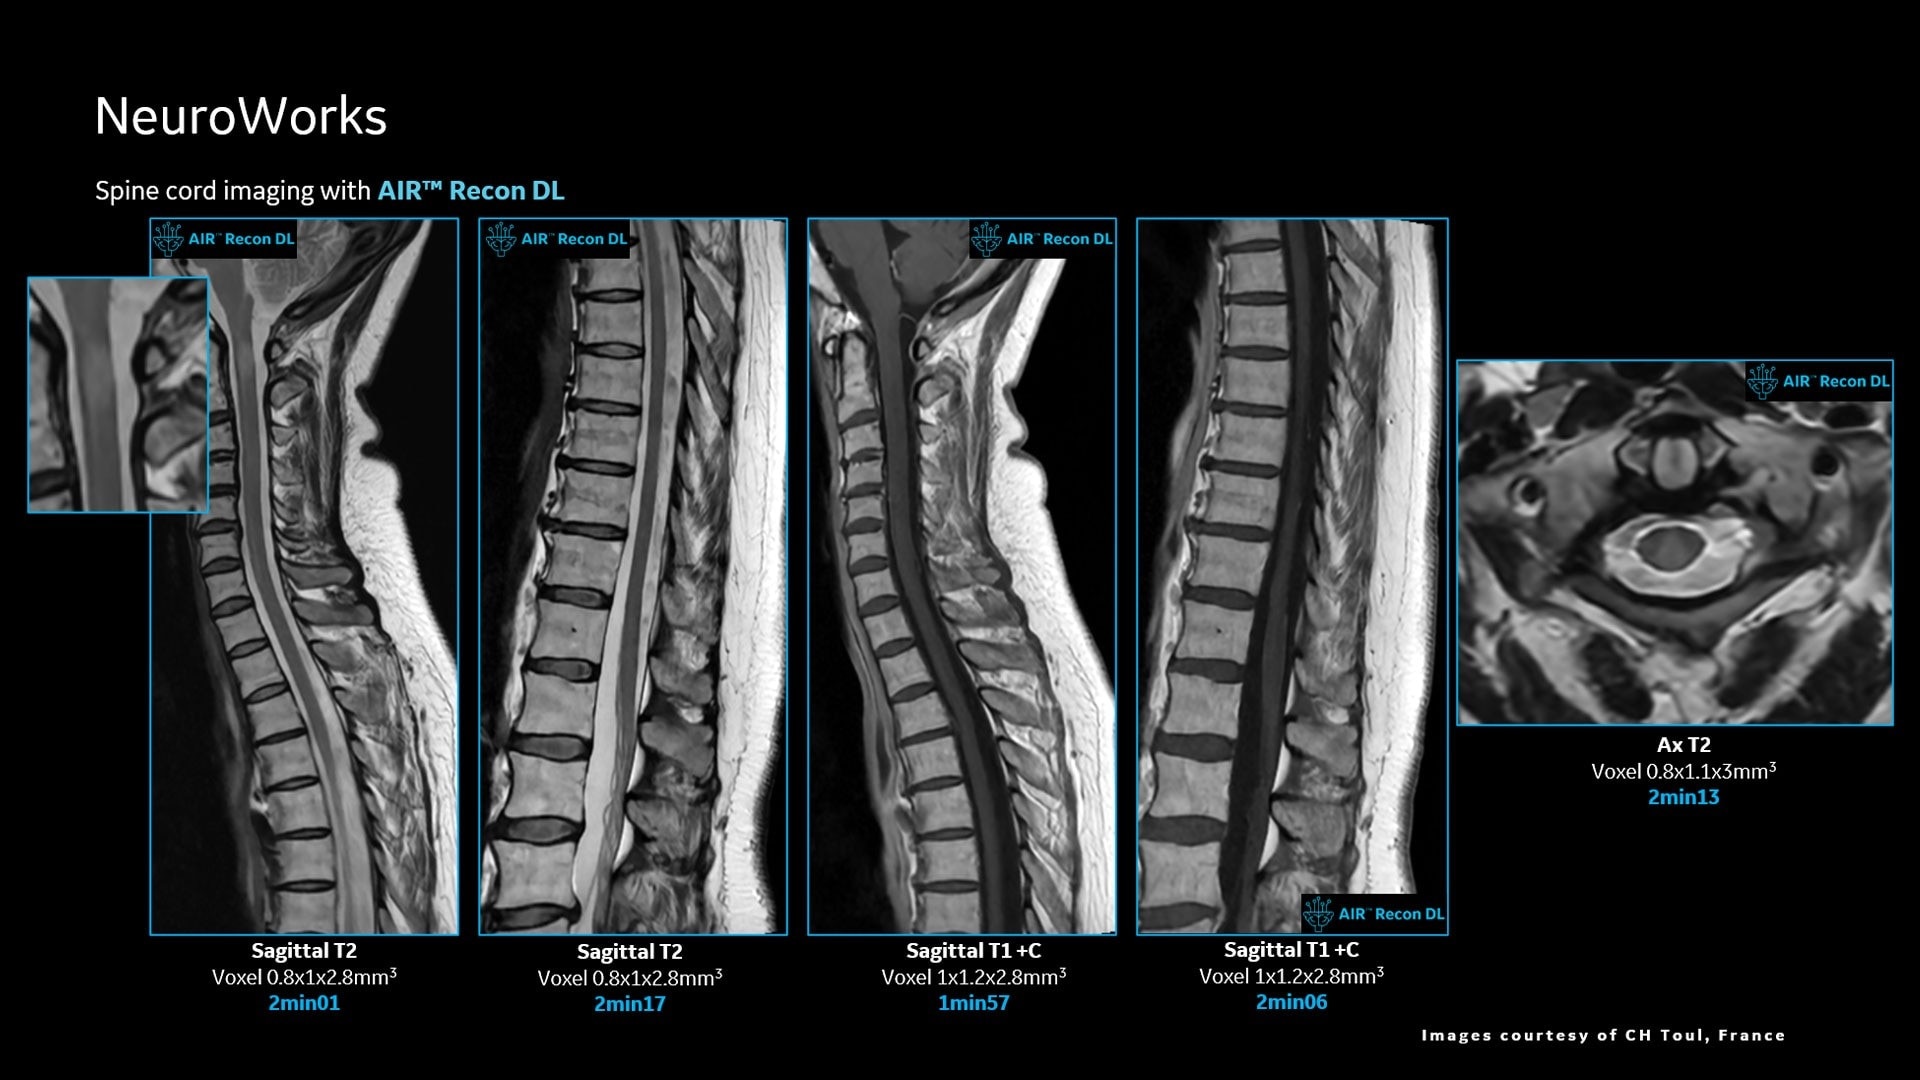

AIR™ Recon DL improves SNR and image sharpness, enabling shorter scan times

Up to 50% faster acquisition time with AIR™ Recon DL

Achieve a 25% efficiency gain with Ultra High Efficiency (UHE) gradient system. Fast, clear Total Digital Imaging (TDI) increases SNR by 25%. Improved IQ in 80% of cases without added time. Acquire higher SNR without a time penalty and get images virtually free of artifact with AIR™ Recon DL.***

Attain a 59% productivity gain in exam setup and 37% reduction in table time with AIR Touch™. Five times faster set-up time and four times fewer mouse clicks with AIR x™. Achieve up to a 50% faster acquisition time with AIR™ Recon DL.***